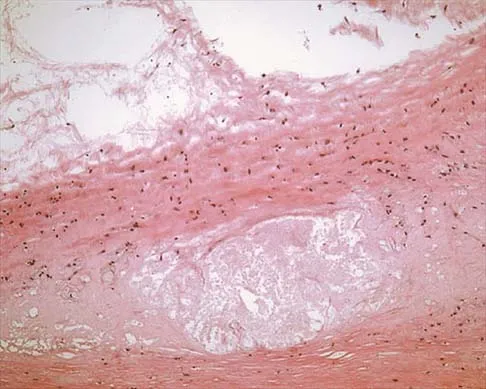

A 16-year-old boy has had thigh pain for the past several months. He denies any history of trauma. Examination reveals a large, deeply fixed, soft-tissue mass in the thigh. Laboratory results show an elevated erythrocyte sedimentation rate (ESR) and leukocytosis. A plain radiograph and MRI scan are shown in Figures 1a and 1b. Biopsy specimens are shown in Figures 1c and 1d. What is the most likely diagnosis?